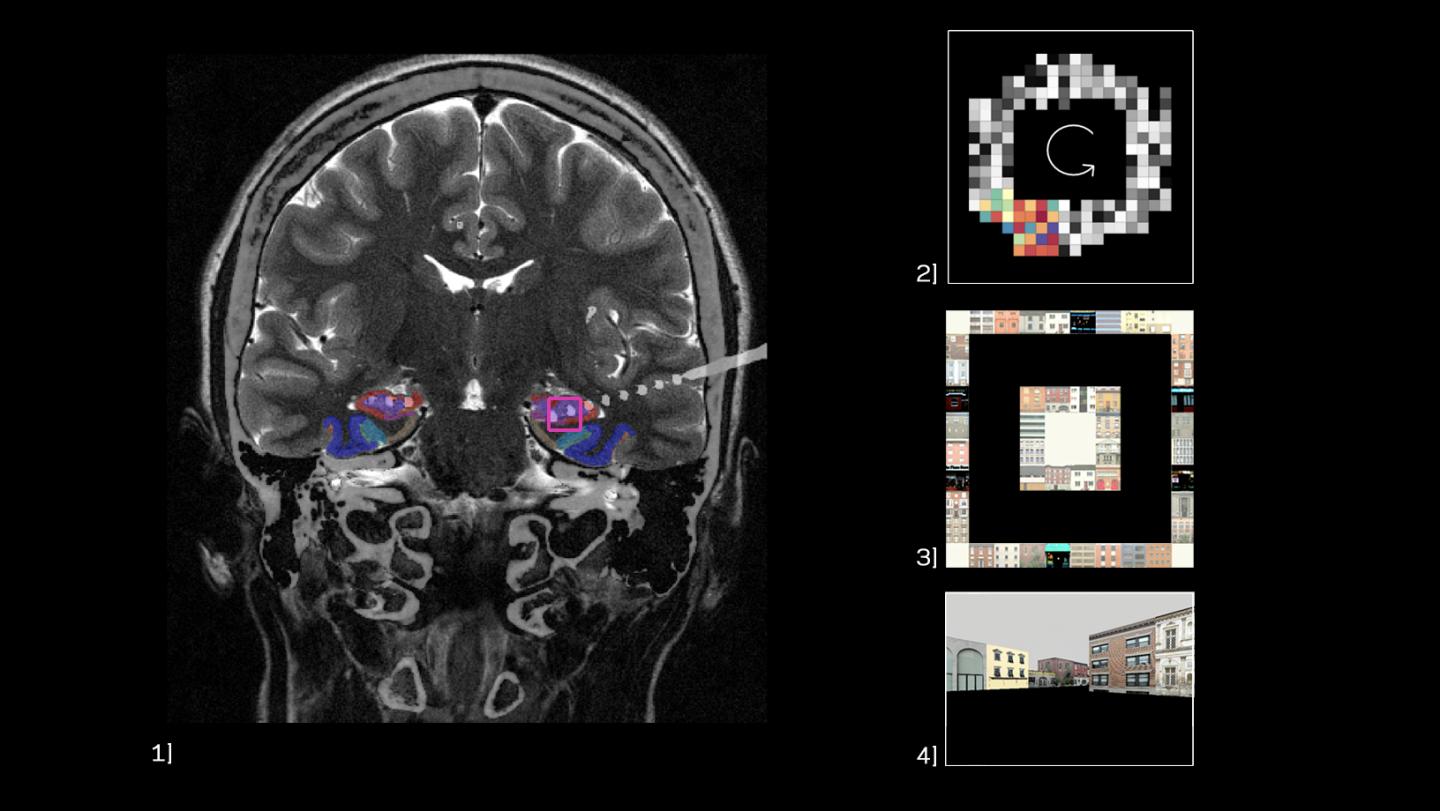

The researchers analyzed direct brain recordings from neurosurgical patients who performed a virtual-reality spatial navigation task in which they had to find and return to six specific buildings. By identifying an internal clock in the form of low-frequency (2-10 Hz) brain oscillations, the team was able to measure how the relative timing of neuronal action potentials correlated with sequential spatial locations, just as in rodents. And what they found especially exciting was that this temporal code extended beyond only representing spatial location to represent the episodic progress subjects had made towards certain goal locations.

The team was able to measure the activity of single neurons by taking advantage of a rare opportunity: the ability to invasively record from the brains of 13 neurosurgical patients at UCLA. Because these bedridden patients had drug-resistant epilepsy, they already had recording electrodes implanted in their brains for their clinical treatment. They used laptops and handheld controllers to move through virtual environments to complete a spatial navigation task designed by the research team.

As the researchers analyzed the neural data from the patients, they noticed how often neurons seemed to fire in concert with slow brain waves. The team was then able to identify phase precession in the hippocampus as subjects moved through different locations, similar to prior observations in rodents.

Knowing now that this temporal code was present for spatial locations in humans, Qasim next looked for evidence that phase precession tracked more complex cognitive sequences, such as the more abstract progress a person had made towards specific goals (i.e. buildings). To do so, the team had to devise a way to measure the temporal relationship between sparse, inconsistent brain-waves and neural spiking without any reference to spatial position. Once they accomplished this, they were surprised to find evidence for phase precession in the frontal cortex, where it has never been observed before, as subjects sought specific goals.